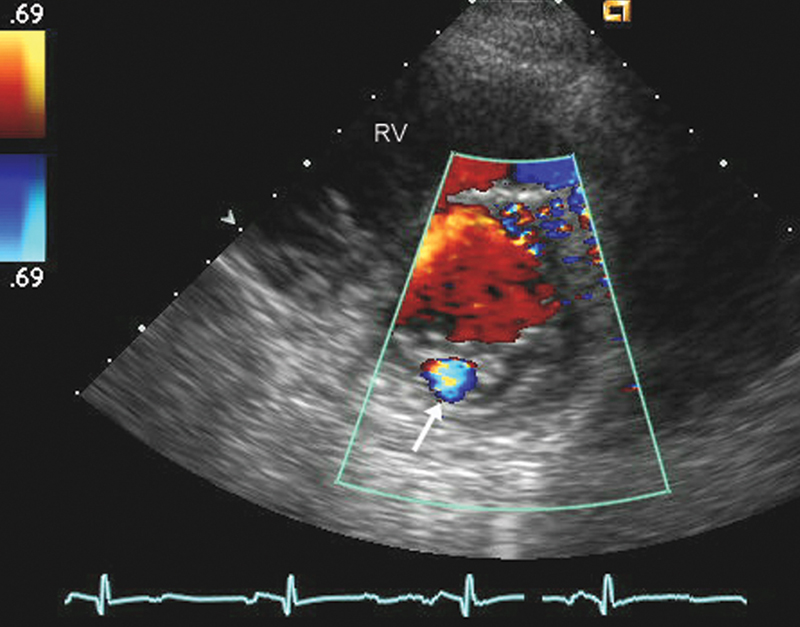

فحوصات تشخيصية لبعض امراض القلب والشرايين التاجية